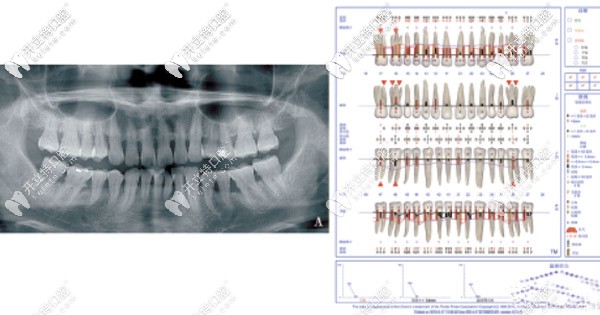

2.jpg▲曲面平展片以及剛檢查的Florida檢查表

顧客存在深覆合、深覆蓋、上下中線不齊、下前牙列擁擠等錯(cuò)頜畸形問題,造成惡劣不利于菌斑控制的環(huán)境。

檢查時(shí)發(fā)現(xiàn)顧客的口腔衛(wèi)生情況較差,牙齦顏色鮮紅,齦緣腫脹后,以上下前牙為重。齦上牙石Ⅱ度,軟垢Ⅱ度,下頜中偏左3mm,下前牙牙列擁擠。

根據(jù)制定的新分類來看,屬于牙周炎第Ⅲ階段,B級。根據(jù)評估系統(tǒng),評估為高風(fēng)險(xiǎn)。

PD≥5mm的位點(diǎn)數(shù)是疾病進(jìn)展的重要因素,顧客在治療前評估為高風(fēng)險(xiǎn),目前為低風(fēng)險(xiǎn)。同時(shí)還存在咬合創(chuàng)傷,也會加重牙周組織炎癥。